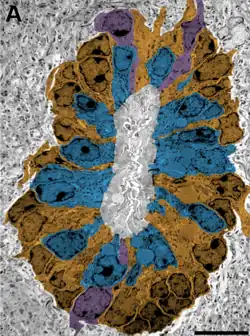

A) Corte transversal del canal.

Las células ependimarias (EpC), exhiben una actividad mitótica basal relativamente baja.[6] El uso de Bromodesoxiuridina (BrdU), que se incorpora al ADN en las células en la fase S, dio como resultado el marcado de 16-24% de las células ependimarias en un mes.